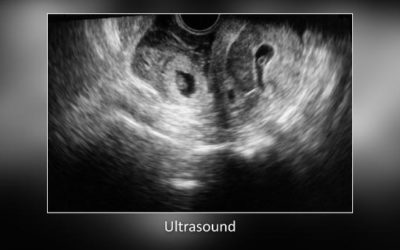

Autosomāli dominantas policistiskās nieru slimības gadījums ar multiplām kompleksām cistām un nieru šūnu karcinomu

Pacientam ar autosomāli dominantu policistisku nieru slimību (ADPKD) un masīvu hematūriju tika veikts ultrasonogrāfijas un krāsu Doplera izmeklējums, kur atrastas multiplas, bilaterālas, aizdomīgas komplicētas cistas un blīvi veidojumi. Rūpīga masu izvērtēšana milzīgā policistiskā nierē, var palīdzēt diferencēt jaunveidojumus no hemorāģiskām vai inficētām cistām. Tomēr ne vienmēr ir viegli atrast, kurš veidojums ir atbildīgs par hematūriju ADPKD pacientam.